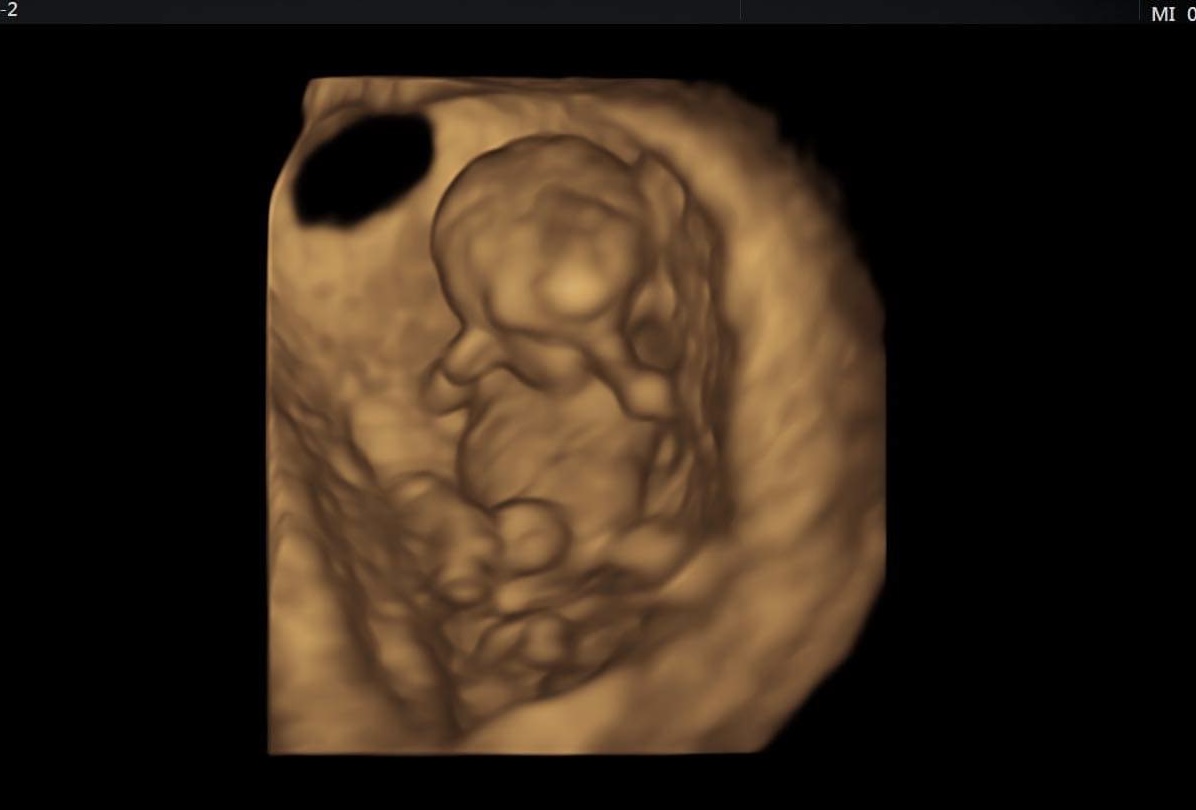

@lenulinka10 Miminko bylo mladší o 12 dní tak to dohání. Podle ultrazvuku co jsem byla dnes tak 10+5tt 😊

@kristynaprandl no to já jsem také zvědavá 🥰 tak na kontrole vse v poradku. Miminko je sice o 5 dní mladší,ale to vůbec nevadí. Krasne si tam kopalo a mavalo ručičkama🥰❤ ultrazvuk ma teda hroznou kvalitu,ale nevadí taky fotečka 🥰